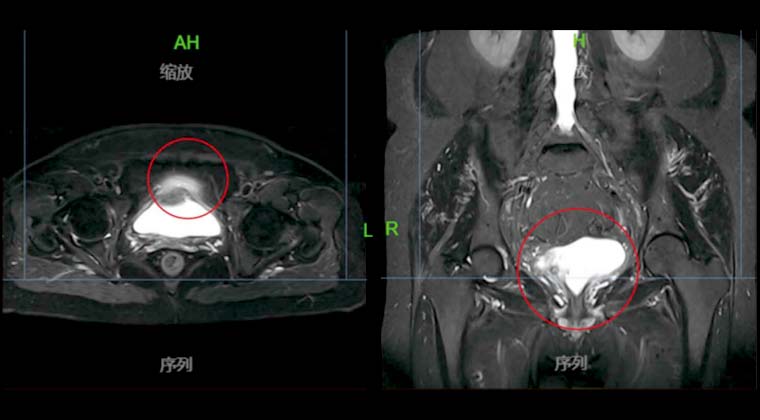

Рак мочевого пузыря

29.02021 проведено PET/CT обследование: выявлены множественные очаги на передней, задней стенках и дне мочевого пузыря, предполагается рецидив опухоли.

Проведена одновременная химиолучевая терапия (монотерапия цисплатином 20 мг/м² еженедельно) с облучением таза по VMAT 45 Гр, с локальным бустом мочевого пузыря 20 Гр, с применением IGRT.

Через месяц после лучевой терапии контрольное МРТ таза не выявило остаточных опухолевых очагов или признаков рецидива в мочевом пузыре.

До лечения:

После лечения: